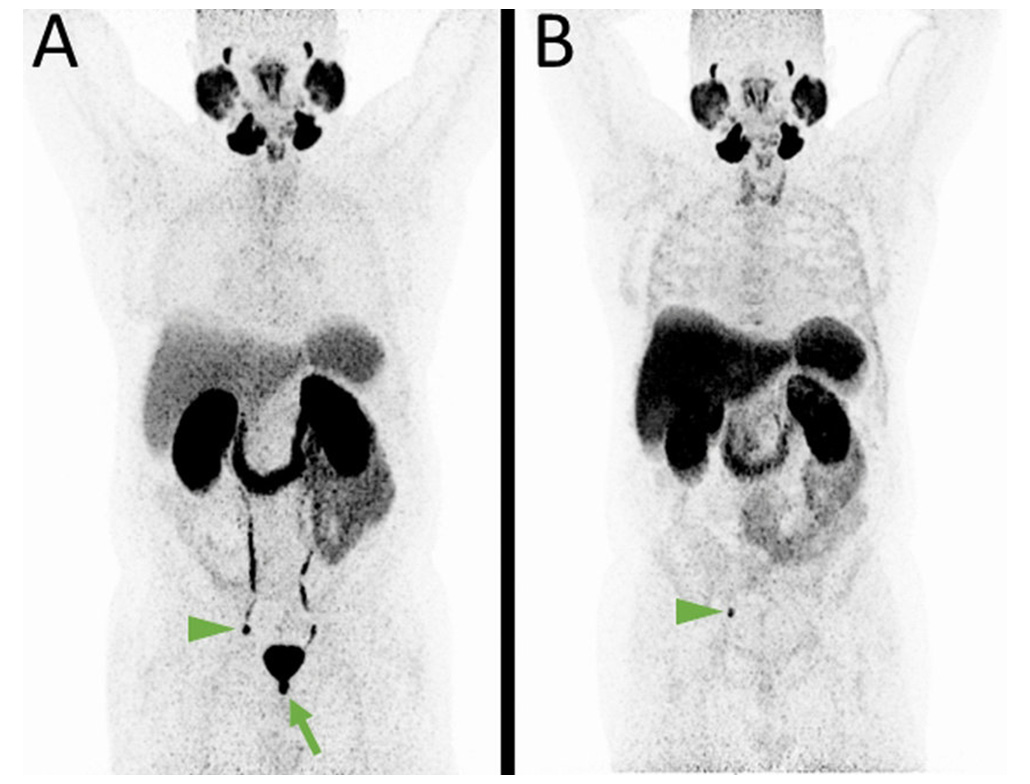

04. 68Ga-PSMA

PSMA-targeted PET imaging agent for prostate cancer diagnosis, treatment response assessment, and recurrence detection.